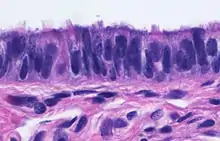

Microanatomy

When viewed under the microscope, the fallopian tube has three layers.[6] From outer to inner, these are the serosa, muscularis mucosae, and the mucosa.[15][16]

The outermost covering layer of serous membrane is known as the serosa.[6] The serosa is derived from the visceral peritoneum.[14]

The muscularis mucosae consists of an outer ring of smooth muscle arranged longitudinally, and a thick inner circular ring of smooth muscle.[6] This layer is responsible for the rhythmic peristaltic contractions of the fallopian tubes, that with the cilia move the egg cell towards the uterus.[14]

The innermost mucosa is made up of a layer of luminal epithelium, and an underlying thin layer of loose connective tissue the lamina propria.[16] There are three different cell types in the epithelium. Around 25% of the cells are ciliated columnar cells; around 60% are secretory cells, and the rest are peg cells thought to be a secretory cell variant.[4] The ciliated cells are most numerous in the infundibulum, and the ampulla. Estrogen increases the formation of cilia on these cells. Peg cells are shorter, have surface microvilli, and are located between the other epithelial cells.[6] The presence of immune cells in the mucosa has also been reported with the main type being CD8+ T-cells. Other cells found are B lymphocytes, macrophages, NK cells, and dendritic cells.[16]

The histological features of tube vary along its length. The mucosa of the ampulla contains an extensive array of complex folds, whereas the relatively narrow isthmus has a thick muscular coat and simple mucosal folds.[14]

Image showing the right fallopian tube (here labeled the uterine tube) seen from behind. The uterus, ovaries and right broad ligament are labeled. Cross-section of fallopian tube, stained and viewed under microscope

Cross-section of fallopian tube, stained and viewed under microscope